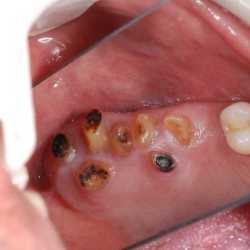

Inicio Especialidades Cirurgia